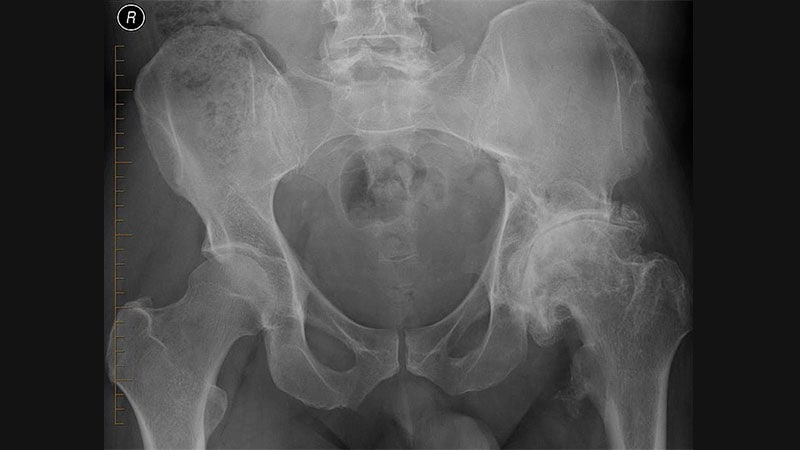

Hospital for Special SurgeryHSS, Arthritis Foundation Spotlight Neglected Hip OA Research -